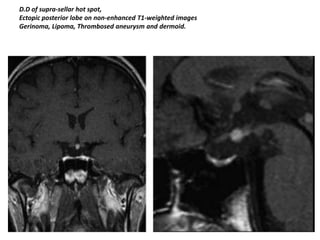

D.D of supra-sellar hot spot,

Ectopic posterior lobe on non-enhanced T1-weighted images

Gerinoma, Lipoma, Thrombosed aneurysm and dermoid.